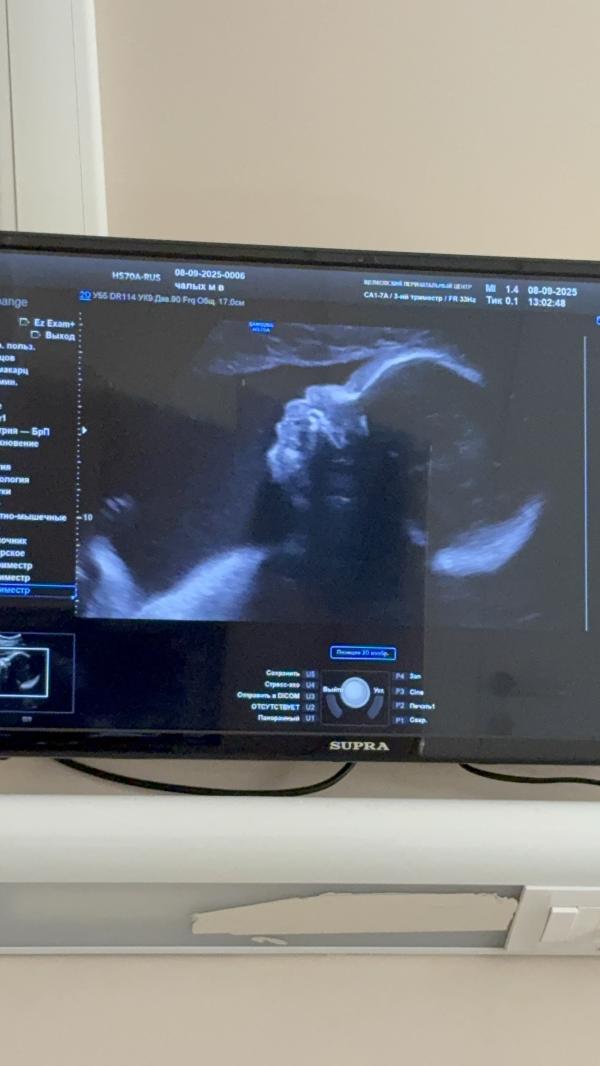

Эмоции после УЗИ: плацента поднялась, счастье переполняет

Вчера сходила на узи платно. Увидела нашу малышку. Все хорошо, плацента поднялась.

Шла домой ревела, как эмоции переполняли)